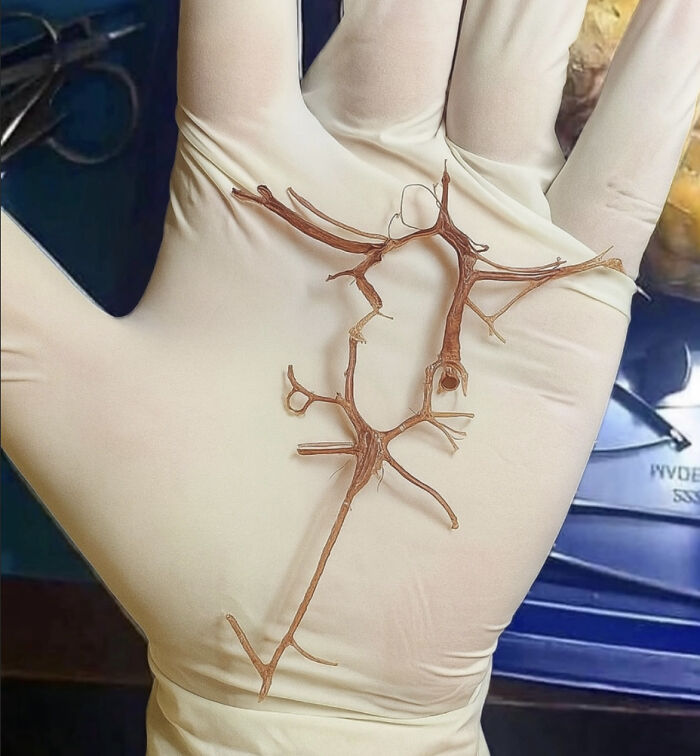

This Is The Circle Of Willis, A Vital Arterial Ring At The Base Of The Brain